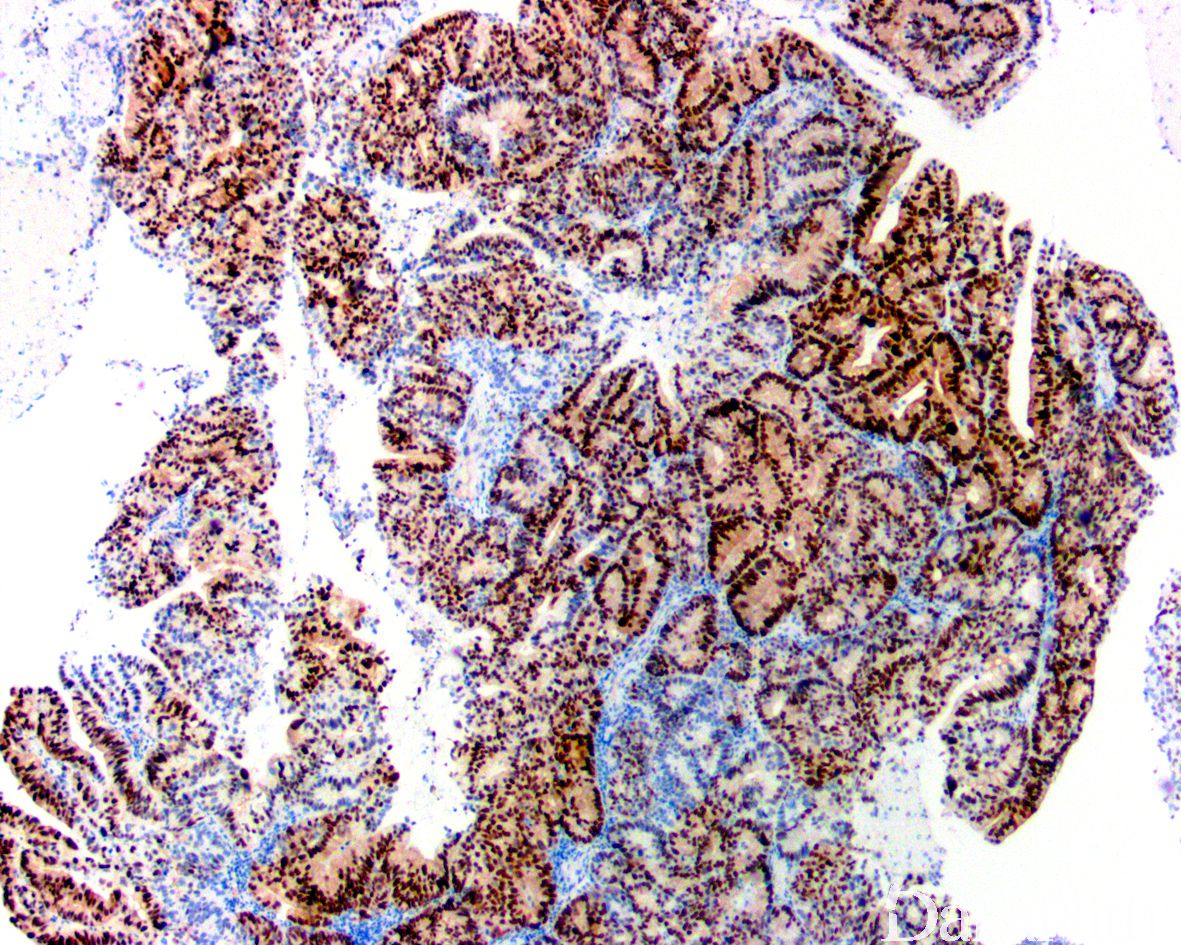

形态学同发生于女性生殖道的子宫内膜样腺癌,可有不同分化程度;

高分化者由分化好的子宫内膜样腺体构成,可伴有鳞状分化、黏液分化及其它化生性改变。

诊断膀胱原发的子宫内膜样腺癌需要满足以下条件:(1)存在子宫内膜异位症病史或者肿瘤与子宫内膜异位症共存;(2)组织学上为非典型子宫内膜样腺体和相关的浸润性癌伴或者不伴有鳞状分化;(3)免疫组化染色表达 ER 和 PR;(4)排除原发的尿路上皮癌,排除转移性癌。

PAX8. ER、PR 阳性。GATA3 通常阴性。